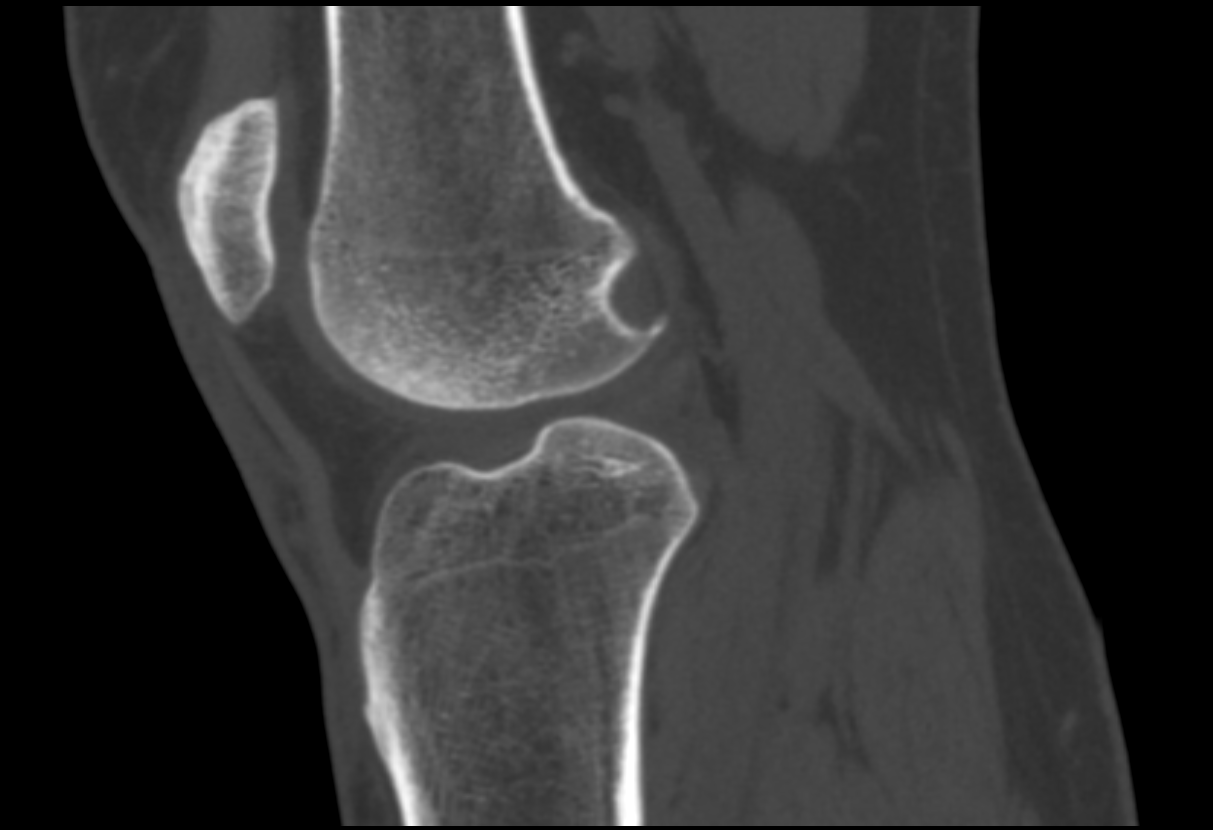

A tomografia em questão é o exame que analisa a articulação do joelho e os ossos, como fêmur, tíbia, patela e fíbula.